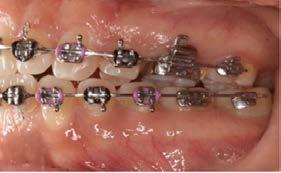

Objetivo: presentar un caso clínico de paciente con mordida abierta anterior, clase II y deglución atípica tratada con aparatología fija ortodóntica.

Caso clínico: paciente femenino de 19 años, patrón dolicofacial, perfil convexo, clase II esqueletal debido a una retrusión mandibular, mordida abierta anterior esqueletal, clase II molar, clase canina no establecida por mordida abierta, apiñamiento severo superior e inferior y deglución atípica.

Resultados: obtención de una clase canina I y clase molar II funcional, se corrigieron las sobremordidas horizontal y vertical, y se logró la coincidencia de líneas medias facial y dental. El manejo de la mordida abierta anterior se llevó a cabo por medio de la corrección del hábito de deglución atípica con la ayuda de spikes de resina, elásticos intermaxilares y arcos utility, y se obtuvieron buenos resultados estéticos, dentales y funcionales.